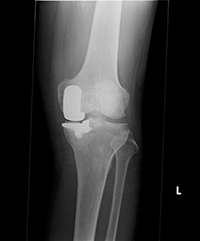

人工膝関節置換術

TKAとUKAの

術後レントゲン